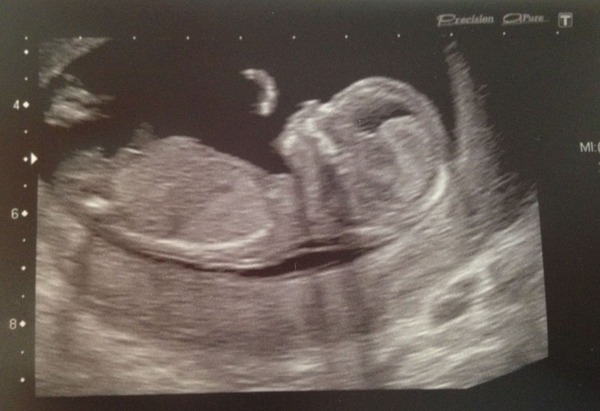

Lovely pictures ladies!

14 & 3 today